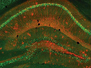

The glymphatic system is the brain’s very own rubbish collection service. Using perivascular channels, the space surrounding the brain’s blood vessels, the glymphatic system is driven by the pulses emitted by these vessels to quickly carry healthy cerebrospinal fluid into the brain and clear out waste. Importantly, the system is thought to remove peptides that form the amyloid plaques found in patients with Alzheimer’s disease. Since the glymphatic system relies on the brain’s network of blood vessels, scientists sought to find out more about the system by studying a rat model of hypertension [high blood pressure]. By tracking the movement of a tracer through the cerebrospinal fluid (illuminated here in red), the team found that the glymphatic system was compromised in rats that had both early and late stages of hypertension. These findings shed new light on the importance of healthy blood vessels in the ageing population to potentially protect against Alzheimer’s disease.